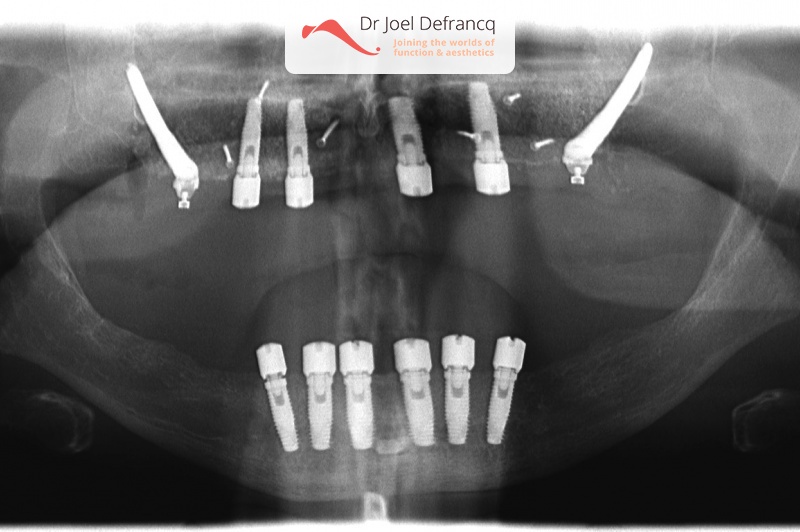

Behandeling tandheelkundige implantaten

- Vaste tanden op implantaten (bovenkaak)

- Vaste tanden op implantaten (onderkaak)

- Zygoma implantaten

- Implantaten met beenopbouw